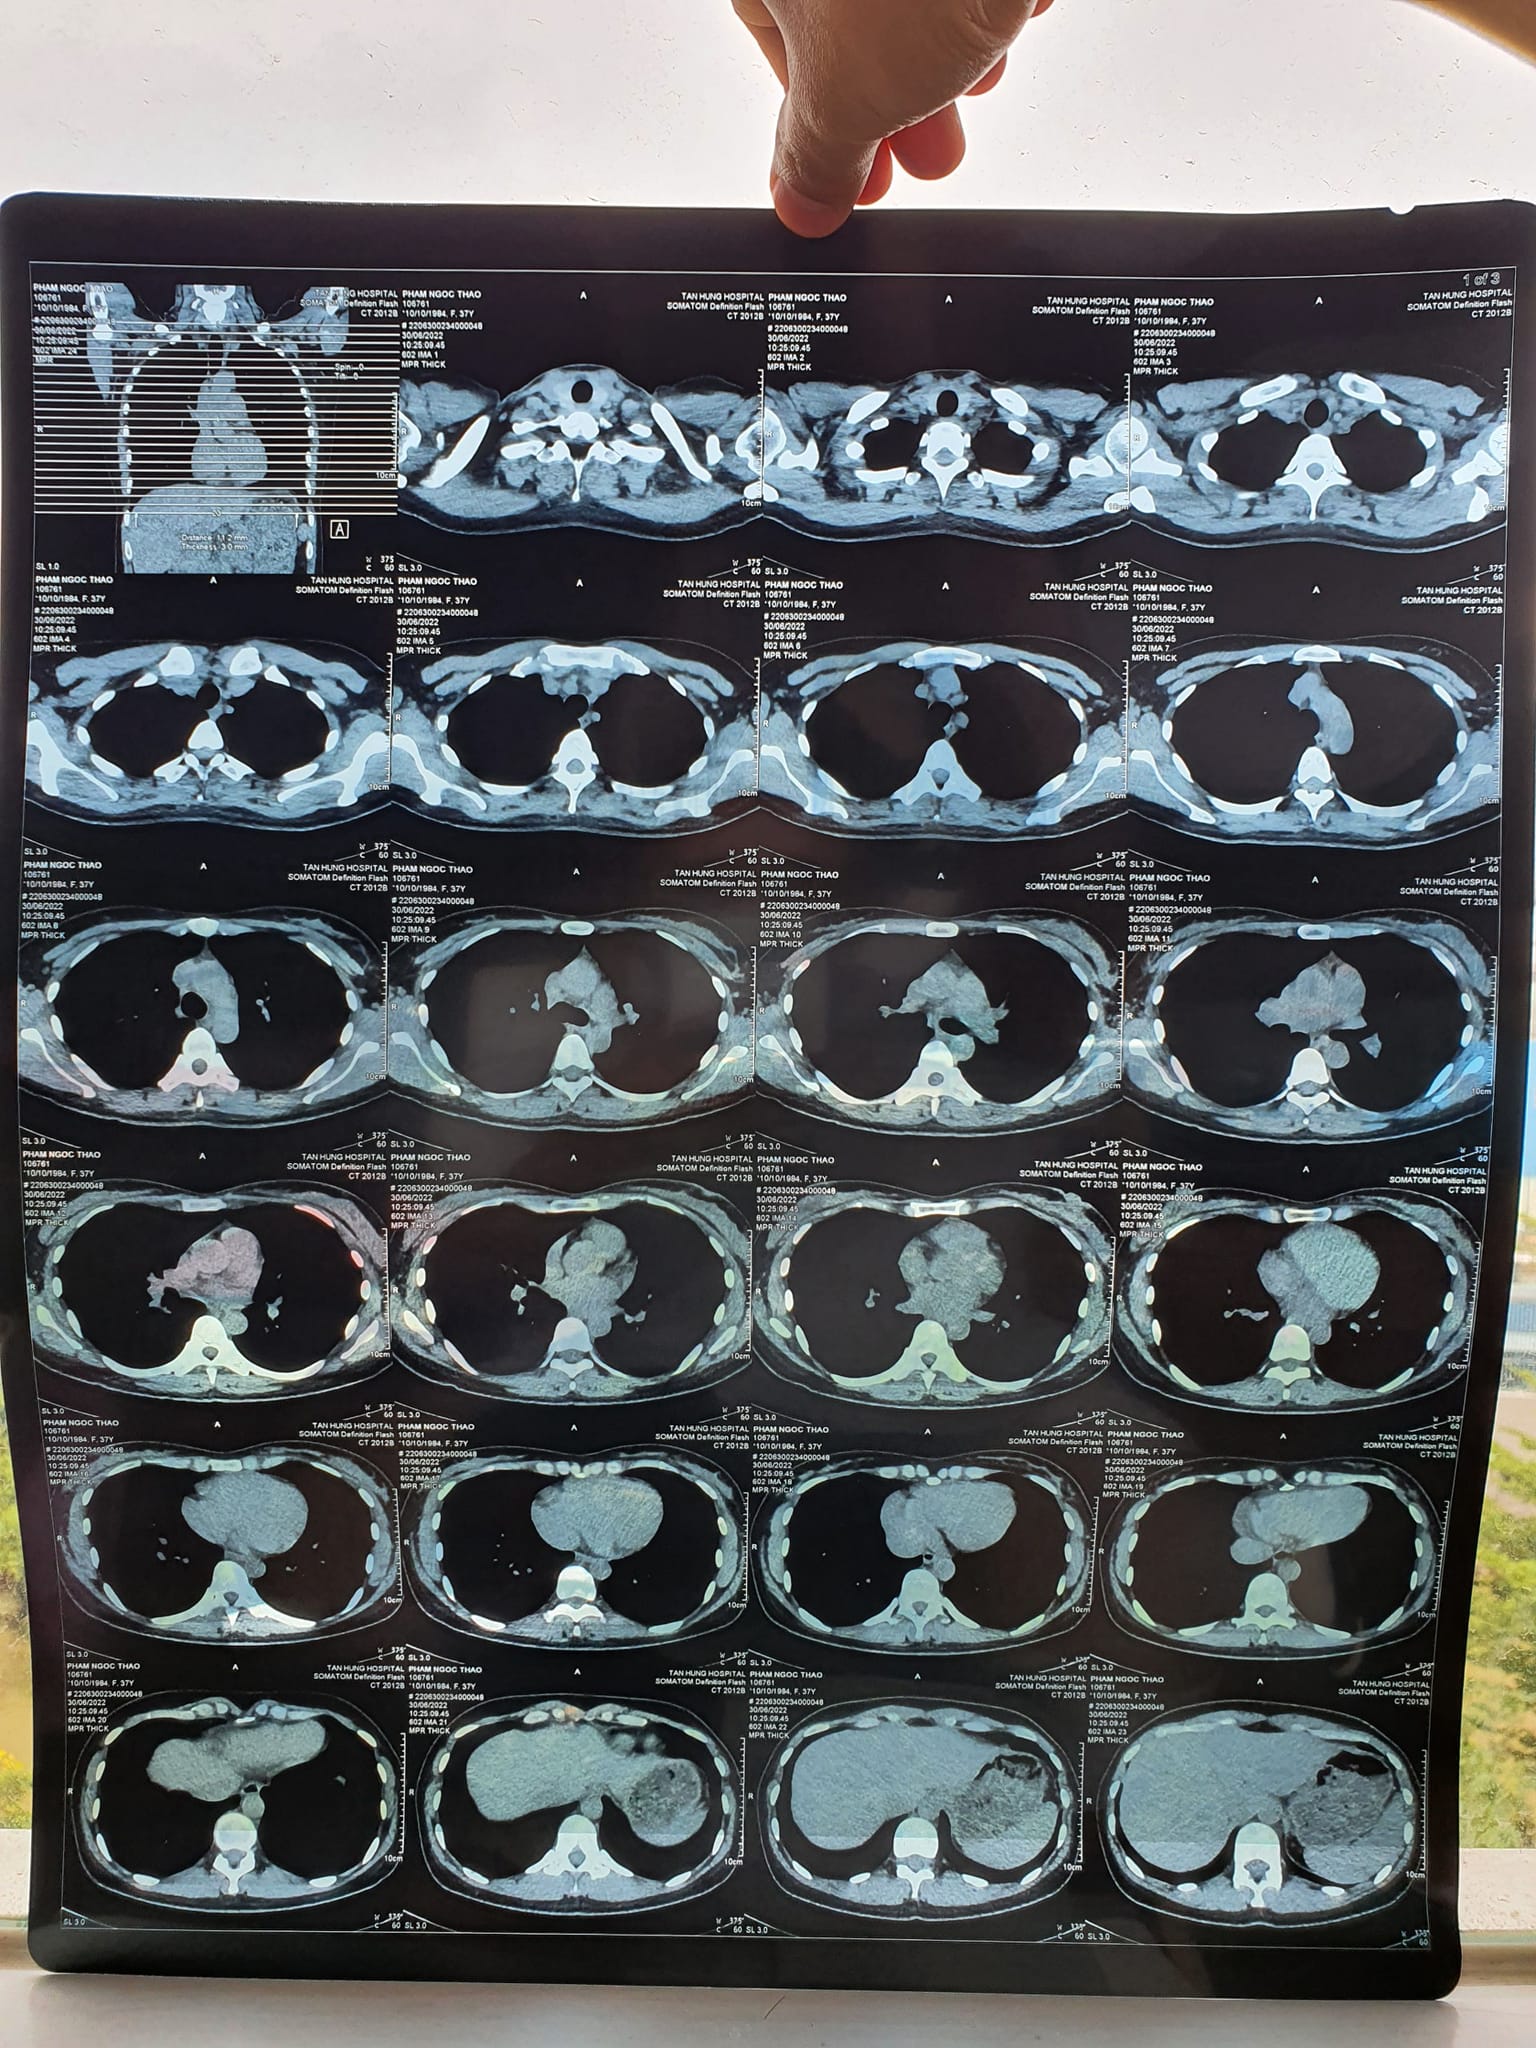

“Thầy còn nhớ ca bệnh năm ngoái chữa viêm phổi cho vợ em không? Thầy chữa 2 tuần liên tục đỡ rồi vợ em về không phải uống thuốc và sinh được bé nhà em. Giờ có biểu hiện lại vợ em đi khám thì có khối u trong phổi. Nên em không thực hiện mổ theo lời bác sĩ nữa mà em muốn nhờ thầy chữa tiếp ạ. Chữa bằng Năng lượng sinh học 2 tháng sau thì chụp X quang lại và CT lại cho kết quả. Chụp X quang thẳng không thấy tổn thương nữa, xong bác sỹ nói chụp nghiêng cho rõ hơn cũng không còn tổn thương. Rồi em yêu cầu chụp CT cho chắc thì kết quả là không thấy khối u nữa ạ. Dạ em cảm ơn thầy nhiều nhiều nhé”

Kết quả X quang và CT sau khi chăm sóc sức khỏe bằng Năng lượng sinh học vào ngày 30/6/2022